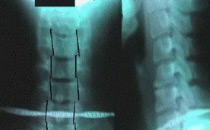

颈椎

例子

病症描述:病变发展至胸椎和颈椎椎间小关节,间盘间隙发生钙化,纤维环和前纵韧带钙化、骨化、韧带骨赘形成,使相邻椎体连合,形成椎体间骨桥,呈较有特征的"竹节样脊柱"。